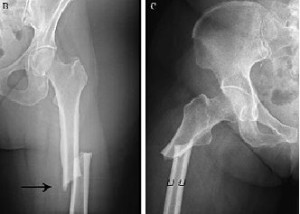

Una revisión sistemática muestra que el tratamiento con bifosfonatos luego de 3 a 5 años puede reducir las fracturas vertebrales, pero no previene las no vertebrales y aumenta el riesgo de complicaciones infrecuentes pero severas. Annals of Internal Medicine, 23 de abril de 2019